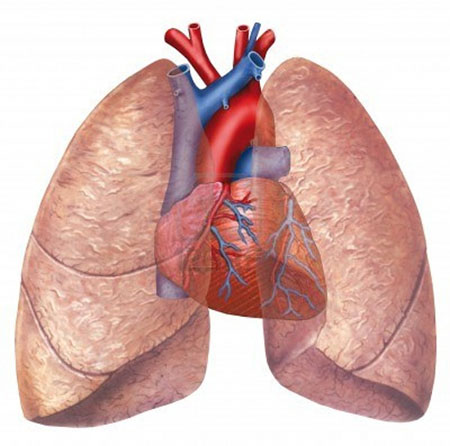

Ağciyərdən inkişaf edən bəd xassəli törəmələrdir, klinik-patoloji xüsusiyyətlərinə görə kiçik hüceyrəli və qeyri-kiçik hüceyrəli növləri var. Proqressiv gedişli xəstəliklərdir.

Ağciyərin bəd xassəli törəmələri mənbəyinə görə iki qrupa ayrılır: birincili və metastatik. Klassik olaraq ağciyərdən inkişaf edən birincili xərçəng klinik-patoloji xüsusiyyətlərinə görə 2 qrupa ayrılır: kiçik hüceyrəli və qeyri-kiçik hüceyrəli.